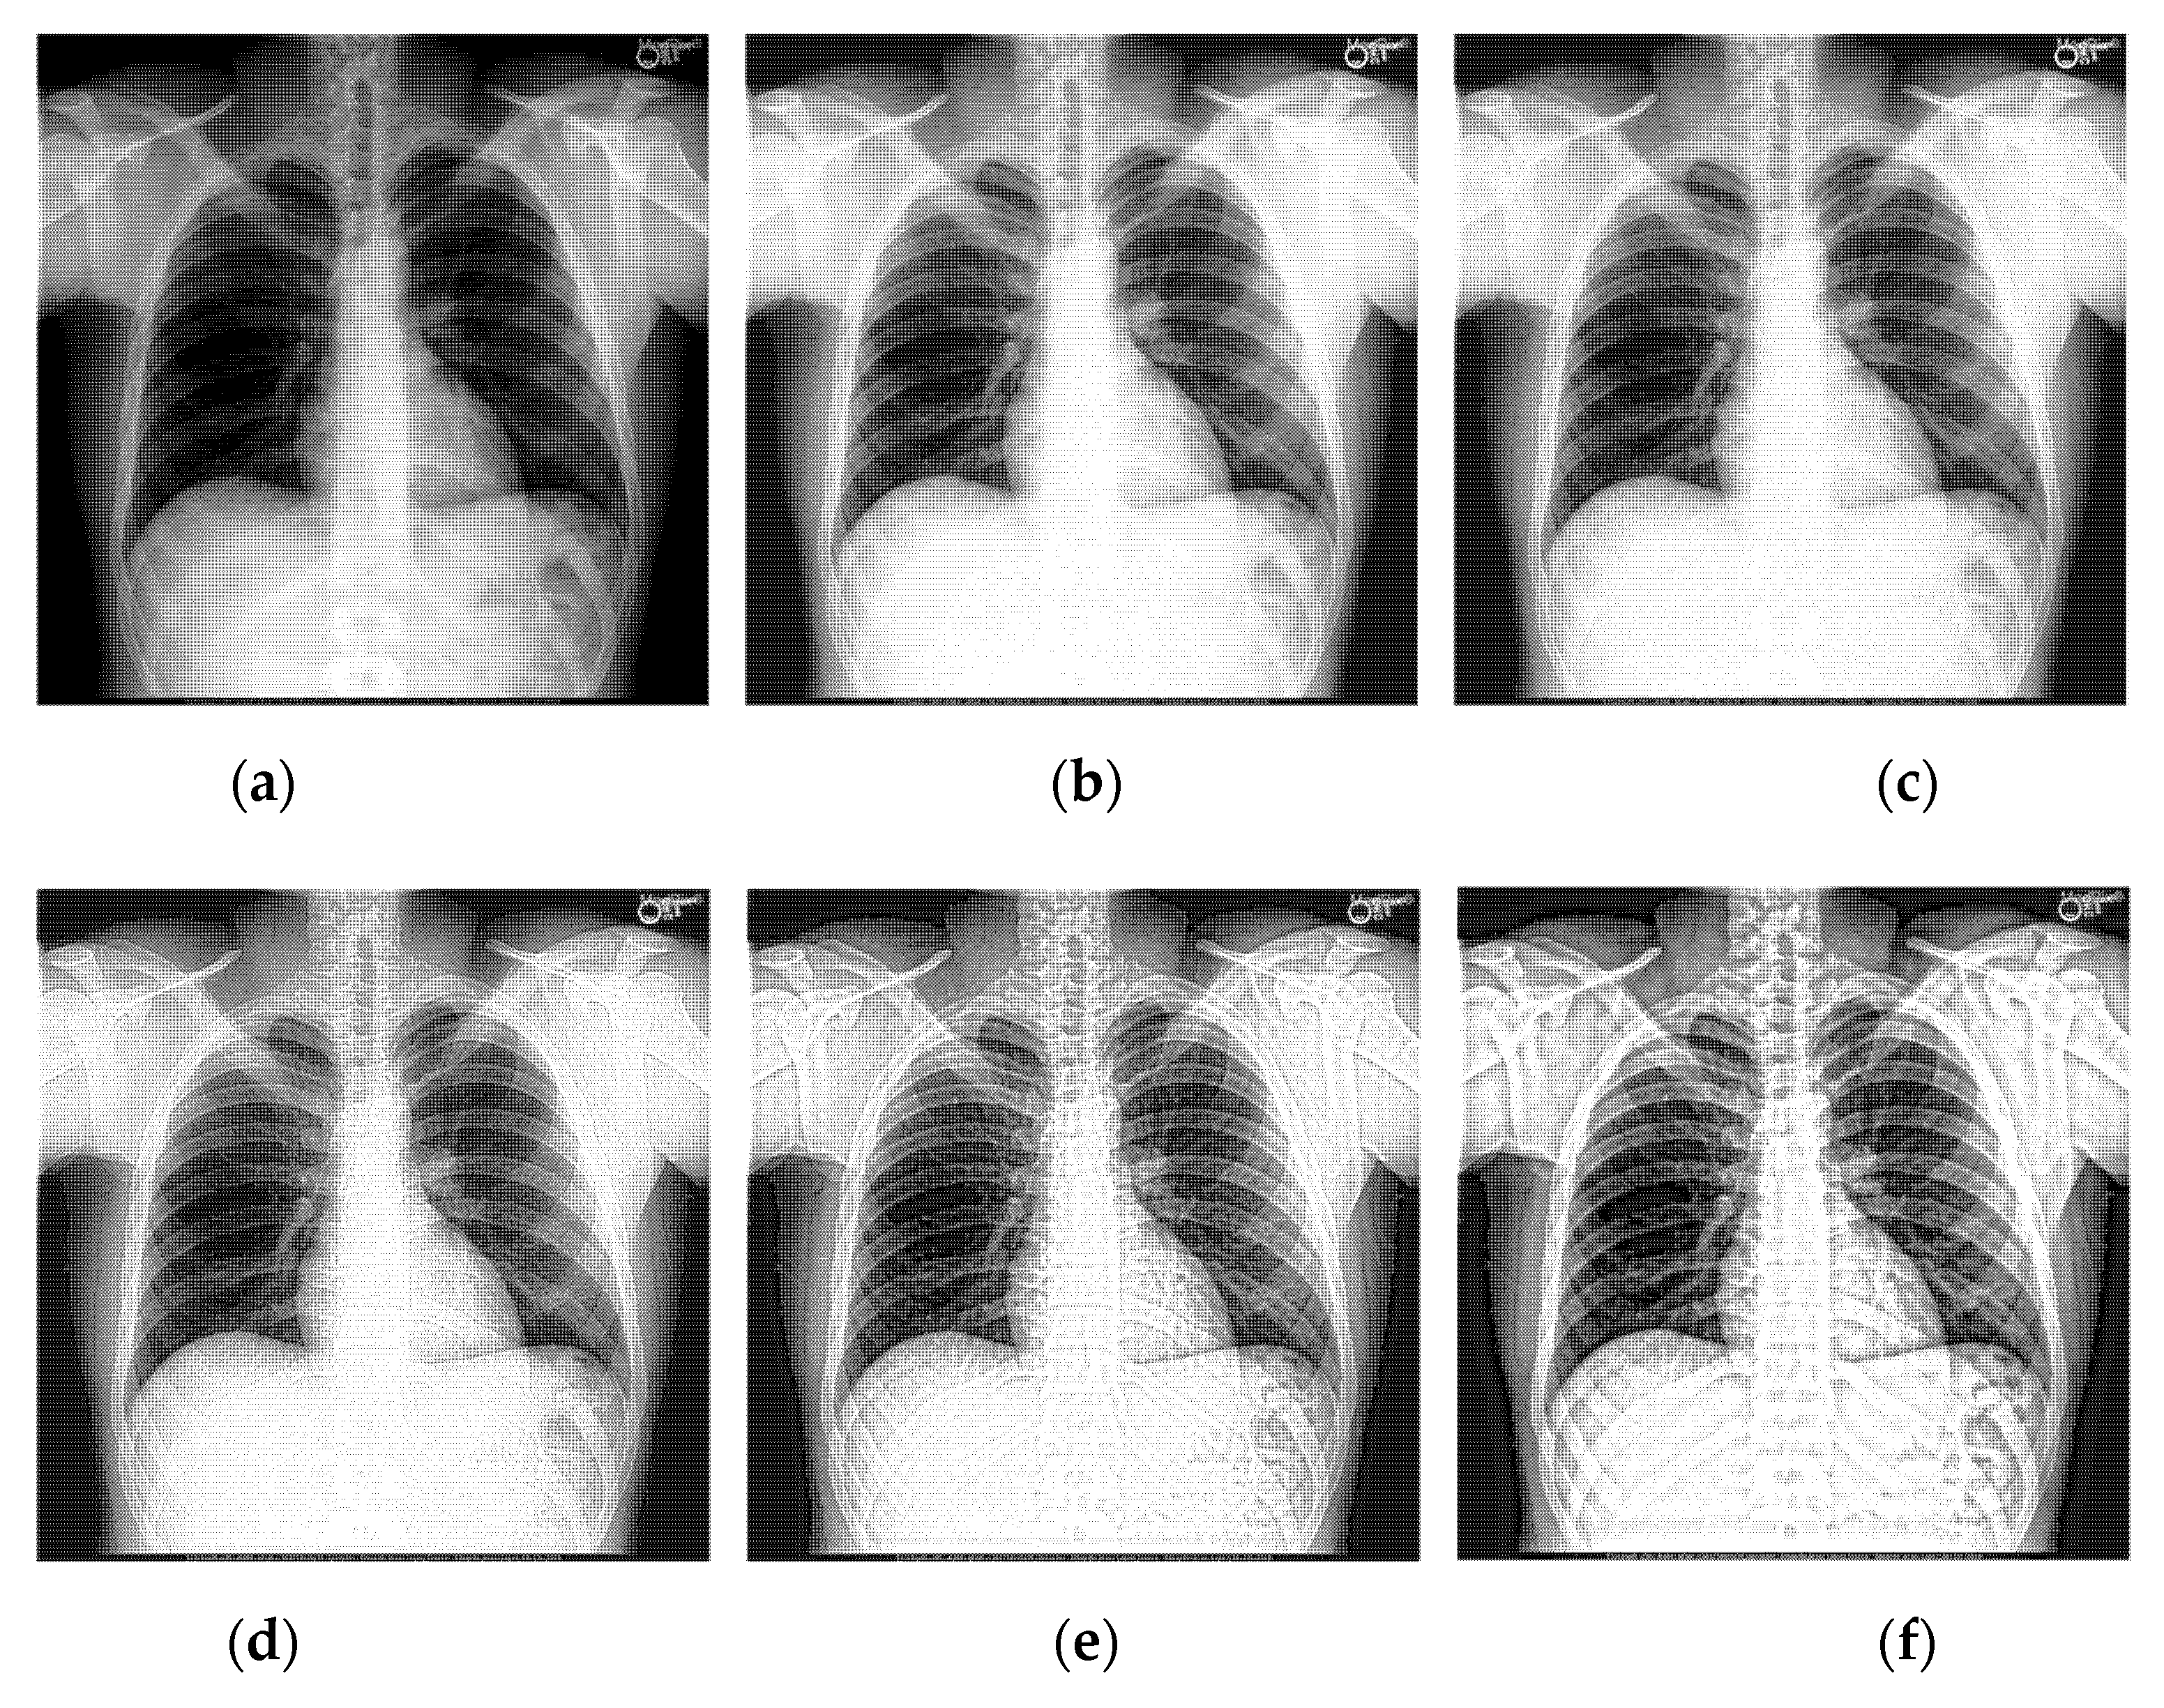

Performing l -level directional decomposition on the high-frequency sub-band image can obtain a 2 l -directional sub-band image of the same size as the source image, achieving more accurate directional decomposition in the frequency domain. The time taken by the 4-level directional decomposition of the NSST algorithm is much longer than that of the 2-level directional one. The shearing directions experiment was carried out on the same batch of pictures by selecting two representative medical images for analysis. The enhanced X-ray images obtained under different shearing directions are shown in Figure 6 and Figure 7. Having analyzed the effects of the shearing directions on image enhancement, the statistical data is shown in Table 3 and Table 4.

Figure 6. The enhanced effects of different shearing directions on X-ray image 1. In (a), the shearing parameters of each level are set to (4,4,4) and the shearing directions are (16,16,16). For (bh), the decomposition scale was set to 4 levels, the shearing parameters of each level are set from (2,2,2,2) to (4,4,4,4), and the shearing directions are from (4,4,4,4) to (16,16,16,16). The number of shearing directions of each level was gradually increased.

Figure 7. The enhanced effects of different shearing directions on X-ray image 2. In (a), the shearing parameters of each level are set to (4,4,4) and the shearing directions are (16,16,16). For (bh), the decomposition scale was set to 4 levels, the shearing parameters of each level are set from (2,2,2,2) to (4,4,4,4), and the shearing directions are from (4,4,4,4) to (16,16,16,16). The number of shearing directions of each level was gradually increased.